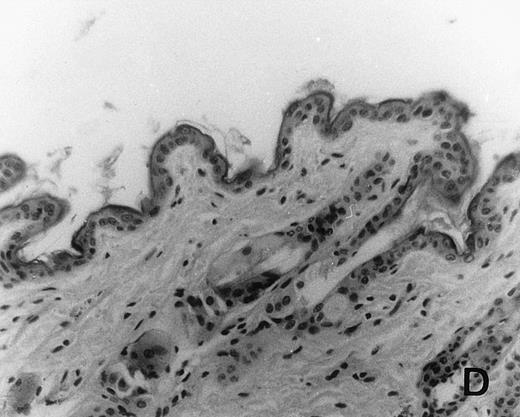

Previous in vitro studies showed that mdm100-specific, allo-restricted CTL killed H-2b tumor cells, including lymphoma cells, but not normal cells.24 However, only a limited selection of normal cells such as dendritic cells and Con-A–activated lymphocytes was available for in vitro tests. Thus, it remained unclear whether some normal tissues in vivo express sufficient levels of mdm-2 to trigger killing by the injected CTL. Several lines of evidence suggested that injected CTL did not attack normal host tissues. Firstly, none of the mice showed any acute side effects after CTL injection. Secondly, the recovery from BMT and the general health status were indistinguishable in mice that received CTL compared with control mice. Thirdly, histological analysis of liver, gut, and skin from 4 CTL treated and 4 untreated mice showed that these tissues, which are normally affected by GVHD, showed similar histology in mice with or without CTL administration (Fig 6). This indicated that CTL injection did not cause the tissue damage that is frequently seen in BMT individuals after infusion of allogeneic T lymphocytes.

Histology of BMT mice. (A through D) The histology of C57BL/6 mice transplanted with B10.A(4R) BM. One group of mice was injected with allo-restricted CTL while the control group did not receive CTL. (A) Liver from a CTL-treated mouse 3 weeks posttransplant, with no significant inflammation or necrosis. (B) Liver from a control mouse 3 weeks posttransplant, with mild periportal inflammation. Skin from a CTL-treated mouse (C) and a control mouse (D) 3 weeks posttransplant, with no significant inflammation or keratinocyte necrosis. Tissues were also examined at 4, 5, and 6 weeks posttransplant and showed no evidence of GVHD in either CTL-treated or control mice (not shown). (E-H) show the histology of (C57BL/6 × BALB/c) F1 mice, transplanted with BM from littermates. One group of mice was injected with allo-restricted CTL and a control group did not receive CTL. (E) Liver from a CTL-treated mouse 4 weeks posttransplant, with no significant inflammation or necrosis. (F) Liver from control mouse 4 weeks posttransplant, with no significant inflammation and necrosis. Skin from a CTL-treated mouse (G) and a control mouse (H) 4 weeks posttransplant, with no significant inflammation or keratinocyte necrosis. Tissues were also examined at 3 and 5 weeks posttransplant and showed no evidence of GVHD in either CTL-treated or control mice (not shown). (All H&E-stained sections, original magnification × 20.) Sections from colon and stomach also showed no significant inflammation (not shown).